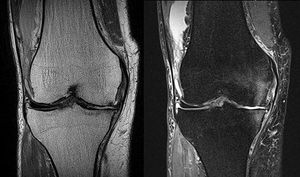

Fat suppression is an important technique in musculoskeletal MR imaging to improve the visualization of bone marrow lesions. Figure: Coronal PD-W TSE (left) and fat suppressed PD-W TSE (right) MR images of the right knee. Fat suppressed PD-W image can visualize the bone marrow edema on the medial condyle of femur and tibia, while no lesion is highlighted on the PD-W image. Image dataset acquired at 1.5 Tesla. Reference: Images courtesy of Bac Nguyen